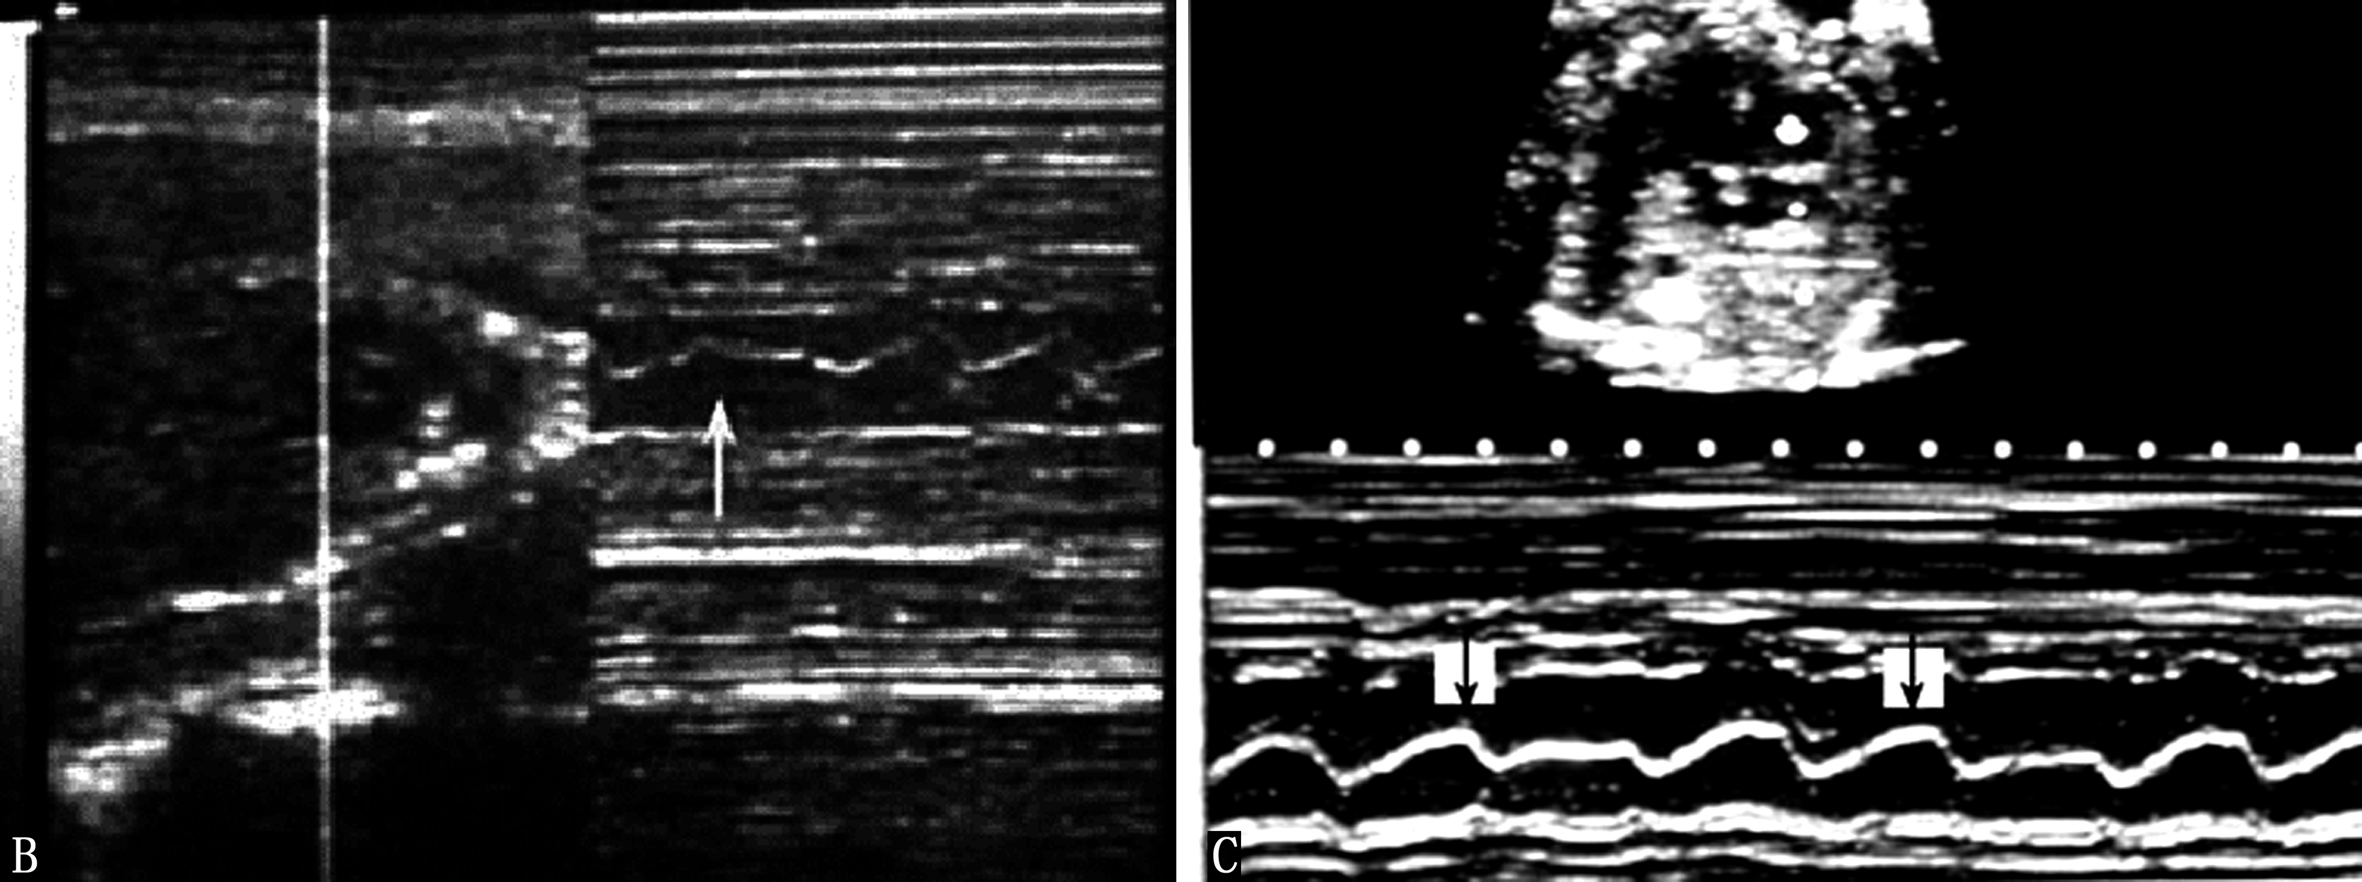

胎儿心律不齐并不少见,但病理性的心律不齐比较少见。和小儿一样,最常见的是窦性心律不齐和早搏。利用胎儿超声心动图和胎儿多普勒超声心动图可以很容易地记录胎儿心脏的异常搏动(图2A-C),并且由于心脏的异常搏动引起的异常血流频谱较心脏活动曲线更容易辨认,但能够提供给临床有价值的信息比较少。根据异常搏动对心室射血的影响程度以及代偿间期有时可以分辨异常搏动的来源,由于胎儿心率较快,分辨时多数有一定的困难。母亲因素,如情绪波动过大、疾病、饮酒、浓茶、过量的咖啡、子宫收缩等,胎儿的因素,如脐带受压、胎儿宫内窘迫、胎儿心脏畸形等均有可能引起胎儿心律失常。发现胎儿心律不齐时应密切观察复查,以判断其临床意义。严重的、持续存在的心律不齐,尤其是严重的室性心律不齐、阵发性心动过速等,可能由胎儿心脏的异常所致。缓慢而不规律的胎心活动常是胎儿凶兆之一。Copel等研究了来自4838个胎儿的5566份胎儿心脏超声检查记录。在595例心律不齐的胎儿中,330例(55.4%)没有发现异常,255例(42.9%)早搏,余10例的心律不齐对胎儿的血流动力学产生了一定的影响,其中9例预后良好,仅有2例合并有心脏发育异常。

图2-B胎心活动曲线记录的异常早搏(左:箭头)及胎心活动曲线记录的二联律(右箭头)

图2-C胎儿心脏二联律引起的血流频谱的改变